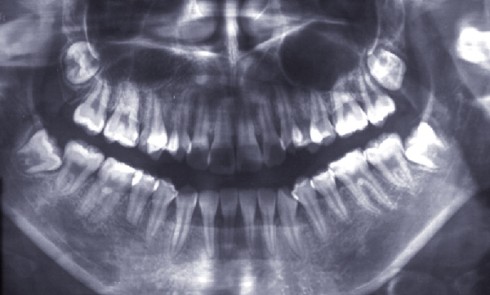

Article réservé à nos abonnés Point sur les indications d’avulsion des dents de sagesse et l’intérêt du CBCT sur les risques chirurgicaux

Les molaires permanentes sont issues d’une prolifération du bord libre de la lame dentaire qui évolue en direction distale (fig. 1)....